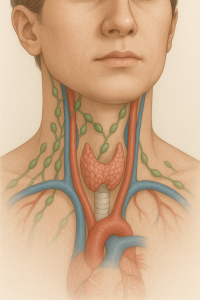

Επεμβάσεις Σιελογόνων Αδένων

Παρωτιδεκτομή: εξωκαψική, μερική, ριζική, αφαίρεση υπογναθίου αδένα, σιαλενδοσκόπηση